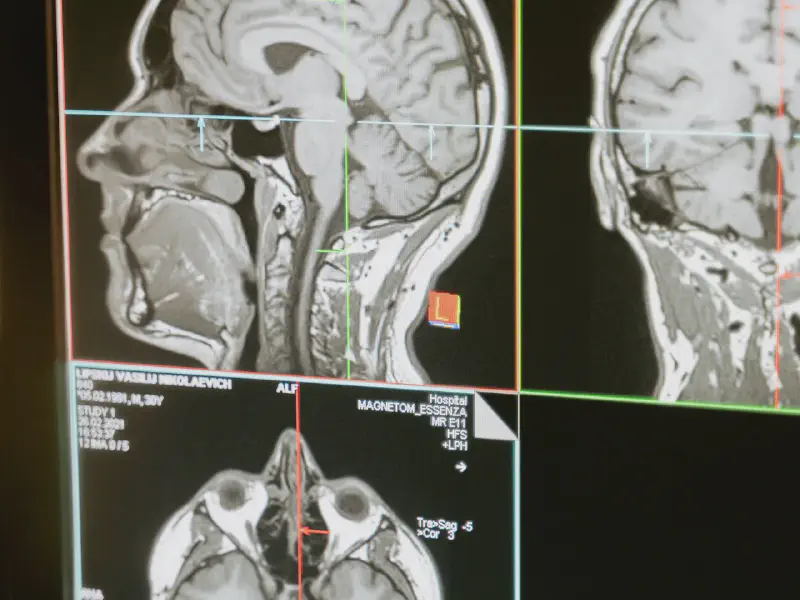

Image not found: medical-technology.webp